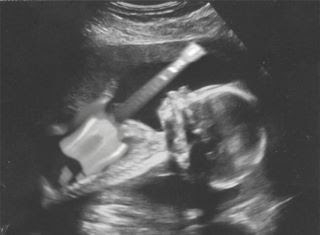

pues eso que voy a ser padre y estoy contentísimo!! el mejor regalo de reyes!!